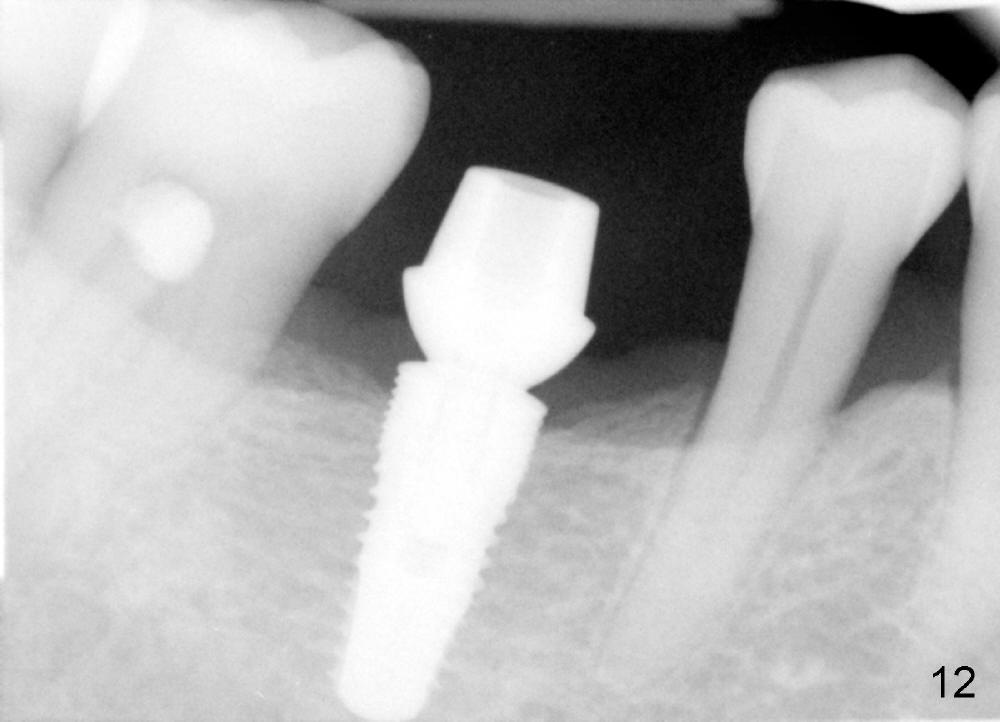

When a positioning pin is placed in the osteotomy with 10 mm deep, the sensor cannot be placed deep enough because of pin interference so no IAC is visible (Fig.4). When the pin is removed and the sensor is placed low enough, IAC is clearly shown, but the osteotomy is barely visible (Fig.5 pink dashed line). With information obtained from pre- (Fig.2,3) and intra- (Fig.4,5) op PA, twelve mm of osteotomy appears to be appropriate. A final implant (5.3x12 mm) is placed with separation from IAC (Fig.6, insertion torque 50 Ncm). A healing abutment is placed (Fig.7,8), which helps retain perio dressing (Fig.9). Two weeks later, the gingiva heals around the abutment (Fig.10). Four months postop, the implant appears to osteointegrate (Fig.11). A cemented abutment is placed (Fig.12). With supragingival margin, oral hygiene is easily maintained (Fig.13). Due to delayed placement, the gingival embrasure is extremely large (*). The issue is much less with immediate implant.